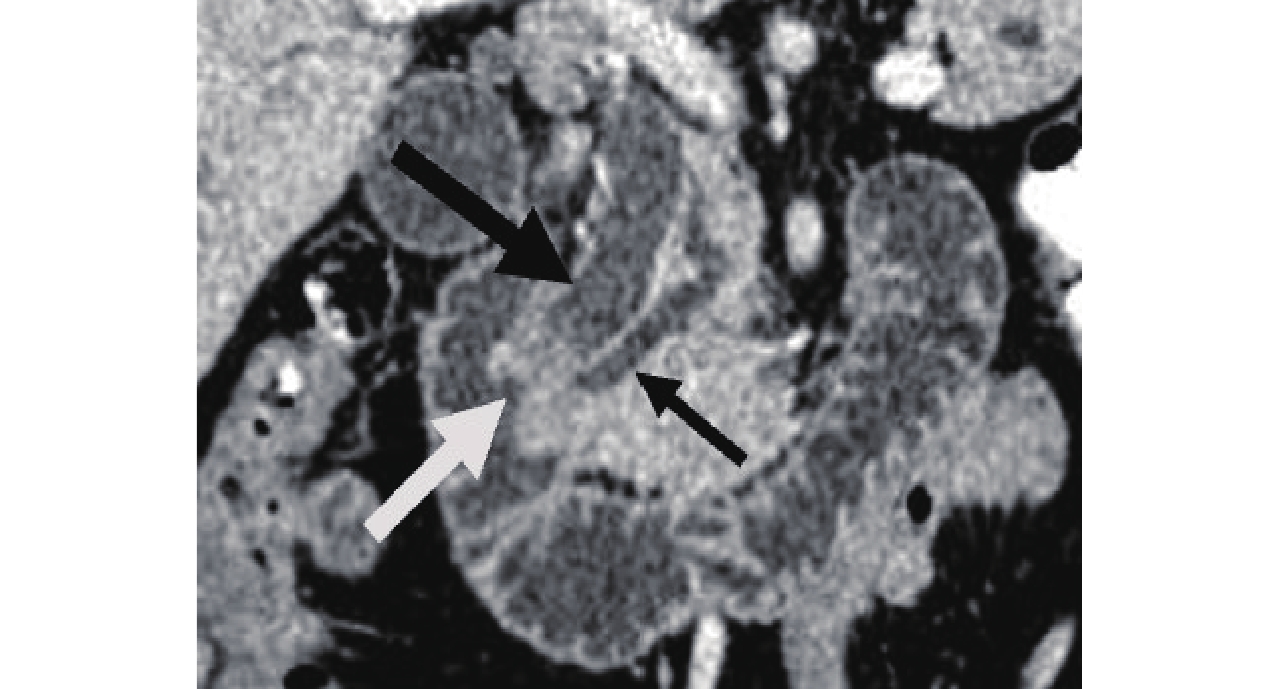

![]() 图 4 CPR显示十二指肠乳头癌表现为十二指肠乳头增大呈葫芦状(倒“3”字形)(白箭头),胆总管(粗黑箭头)、胰管(细黑箭头)扩张并截断于肿瘤Figure 4. CPR, duodenal papillary carcinoma, gourd-shaped (Inverted "3") and enlarged duodenal papilla with enlarged common bile duct (thick black arrow) and pancreatic duct (thin black arrow) which got cut off at duodenal papilla tumor

图 4 CPR显示十二指肠乳头癌表现为十二指肠乳头增大呈葫芦状(倒“3”字形)(白箭头),胆总管(粗黑箭头)、胰管(细黑箭头)扩张并截断于肿瘤Figure 4. CPR, duodenal papillary carcinoma, gourd-shaped (Inverted "3") and enlarged duodenal papilla with enlarged common bile duct (thick black arrow) and pancreatic duct (thin black arrow) which got cut off at duodenal papilla tumor3. 讨论

图 4 CPR显示十二指肠乳头癌表现为十二指肠乳头增大呈葫芦状(倒“3”字形)(白箭头),胆总管(粗黑箭头)、胰管(细黑箭头)扩张并截断于肿瘤

Figure 4. CPR, duodenal papillary carcinoma, gourd-shaped (Inverted "3") and enlarged duodenal papilla with enlarged common bile duct (thick black arrow) and pancreatic duct (thin black arrow) which got cut off at duodenal papilla tumor